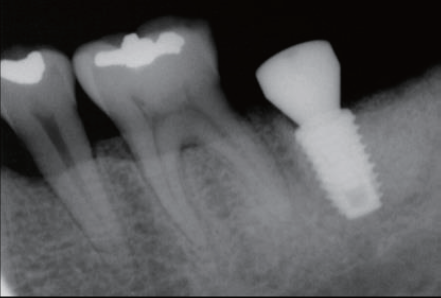

Pre-Op view

Post-Op

Re- entry surgery after 7 month

Final Restoration